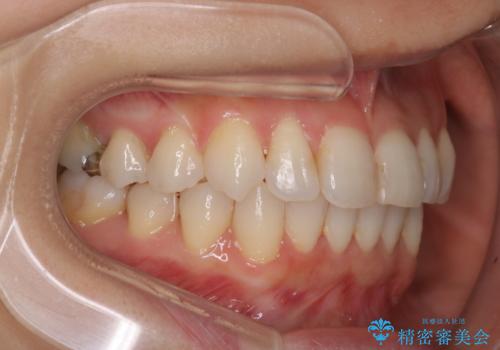

八重歯と前歯のガタガタをインビザラインで

- 八重歯と前歯のガタガタを主訴に来院されました。

目立たず矯正したいとのことでインビザラインで矯正することとしました。

インビザラインで目立たずに治療を終えることができ、喜んでいただけました。